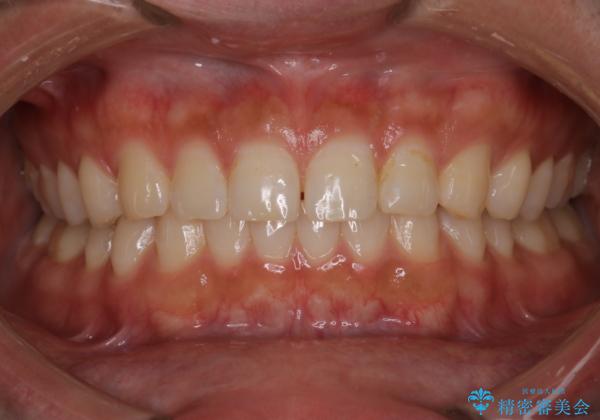

【インビザライン】正中離開を治したい

再矯正ということでがたつきはなくきれいに並んでいましたが、上下のアーチ(歯列弓)の大きさのバランスが悪く、結果的に後戻りの原因になってしまっていました。今回は下のアーチを小さくするためにIPRを行い、かみ合わせのバランスを治しながら前歯の隙間を閉じました。